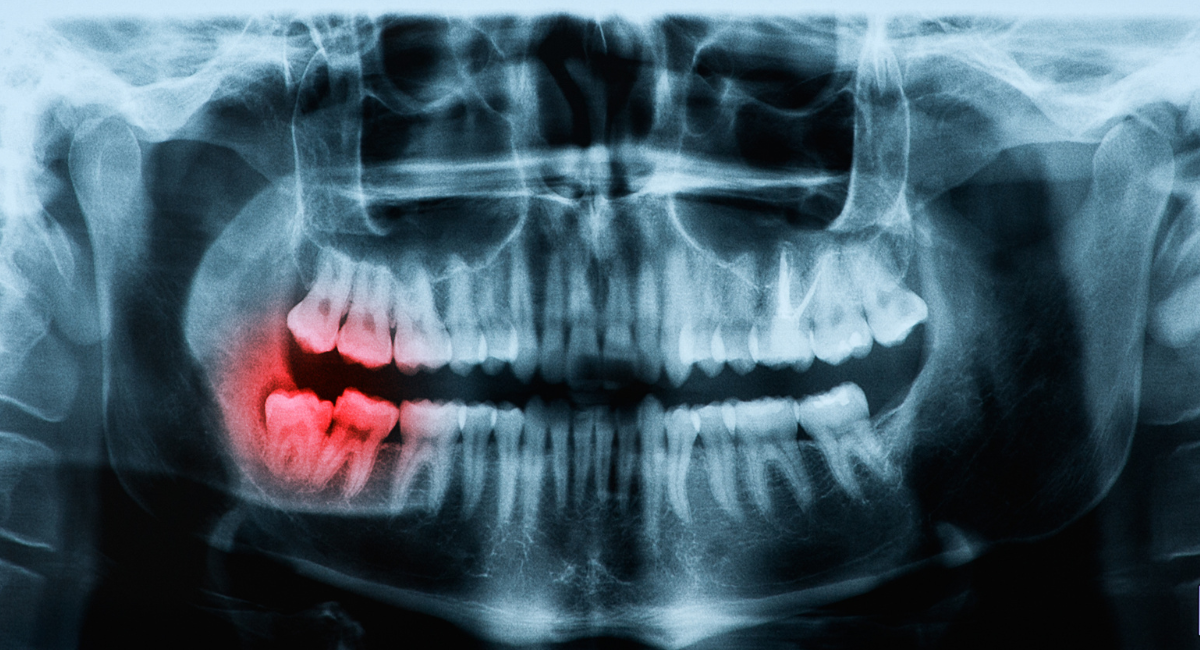

親知らずの抜歯において最も大切なのは、処置そのものよりも事前の診断です。見た目だけで「抜いたほうがよい」「今は様子を見ましょう」と判断するのではなく、歯の根の形や向き、周囲の骨や神経との位置関係まで把握することで、適切な治療方針を立てることができます。

特に下顎の親知らずは、下歯槽神経という重要な神経の近くに位置していることがあり、診断を誤ると術後のしびれなどのリスクにつながる可能性があります。そのため、レントゲンや必要に応じた精密検査を行い、リスクを想定した上で治療計画を立てることが不可欠です。

横に生えた親知らず(中度)

難易度 ★★★

状態

歯ぐきの中に歯が埋まっており、70~80%は骨に埋まっている状態です。「水平埋伏智歯」と呼ばれます。注意事項

術前にCT撮影を行います。処置時間は30分程度です。麻酔後に切開し、歯を割って抜歯したら2~3針縫合します。術後3日程度は腫れるかもしれませんので、鎮痛剤・抗生物質を服用してください。 -

完全に骨に埋まった親知らず

難易度 ★★★★

親知らずが骨の中に埋まっている状態です。慢性的に排膿(はいのう)しています。注意事項

術前にCT撮影を行います。処置時間は45分程度です。麻酔後に切開し、神経の損傷を避けて抜歯したら2~3針縫合します。同時に歯周病の治療も行います。術後は腫れますので、鎮痛剤、抗生物質を3~5日服用してください。 -

完全に骨に埋まり歯根が神経に近い親知らず

難易度 ★★★★★

親知らずが顎の骨の中に埋まり、膿の袋を形成している状態です。神経と歯根が絡みあっています。注意事項

処置時間は左右合わせて60~90分です。入院し、全身麻酔を施したうえで手術を行います。左右を抜歯し、のう胞の摘出をします。神経麻痺が生じる可能性があるので注意が必要です。

レントゲン・CTを用いた正確な診断

親知らずは、見た目だけでは判断できない要素が多い歯です。歯ぐきの中や骨の中に埋まっている場合も多く、歯の向きや根の形、周囲組織との関係性は、外からは分かりません。そのため横浜市鶴ヶ峰駅の歯医者・歯科、横浜グランアズーリデンタルクリニック鶴ヶ峰では、通常のレントゲン検査に加え、必要に応じてCT撮影を行い、立体的な情報をもとに診断を行います。

CT検査によって、

- 親知らずがどの方向に生えているのか

- 歯の根がどの程度まで形成されているのか

- 顎の骨の厚みや形状

- 重要な神経や血管との距離

といった情報を詳細に把握することができます。これにより、抜歯の難易度や想定されるリスクを事前に整理し、無理のない治療計画を立てることが可能になります。